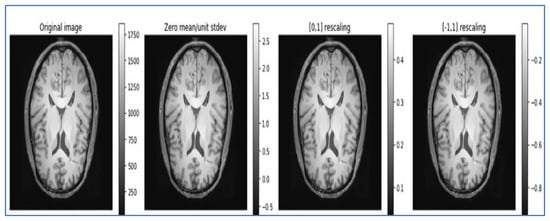

- Data normalization: Data normalization is beneficial for removing different redundancies from the datasets, such as varied contrasts and varied subject poses, to simplify subtle difference detection. It rescales the attributes with a mean value of 0 and a standard deviation of 1. Different types of normalization techniques, such as Z normalization, called standardization; min–max normalization; and unit vector normalization, are applied to the dataset. We applied unit vector normalization to our dataset.

- Unit vector normalization: It shrinks/stretches a vector and scales it to a unit length. We applied it to the whole dataset, and the transformed data are viewed as a cluster of vectors with distant trajectories on the d-dimensional unit sphere. The general formulae for unit vector normalization are , where = normalized vector, = non-Zero vector, and = length of U.